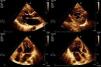

All patients were assessed by two-dimensional color Doppler and three-dimensional echocardiography using iE33 scanners (Philips Medical Systems). Contrast was used in one patient to exclude intraventricular thrombi. The diagnostic criteria of Jenni et al. were used: a ratio of non-compacted to compacted layers of >2 measured in systole; numerous prominent trabeculations and deep intertrabecular recesses filled with blood from the ventricular cavity, demonstrated by color Doppler; and absence of associated cardiac abnormalities.1

In our center we follow the criteria of Jenni et al., as they are the most commonly used. However, as pointed out by several authors,20,21 it can be difficult to obtain rigorous and reproducible measurements of the thickness of the compacted and noncompacted layers, and so all patients also underwent MRI to confirm the diagnosis. This technique, as well as showing good agreement with echocardiographic findings, also has superior spatial resolution that enables better visualization of the LV apex and lateral wall, which are often involved in noncompaction. We consider that images from MRI are particularly suitable for quantitative assessment, for which the standard criteria are those of Petersen et al., as used in this study (see Methods). In 2010, Jacquier et al. showed that measurement of trabeculated LV mass by MRI can be used in the diagnosis of LVNC. According to these authors, a value above 20% of the total mass of the LV has high sensitivity and specificity for the diagnosis of LVNC (Figures 1 and 2).22